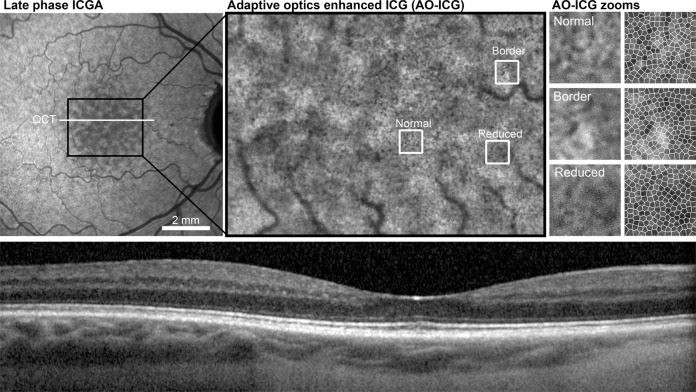

In addition to conventional clinical imaging, the increased resolution capabilities of adaptive optics enhanced indocyanine green (AO-ICG) imaging [4, 5] provided a view of heterogeneously-labeled retinal pigment epithelial (RPE) cells within the ASHS-LIA pattern (Fig. 2). Comparison of RPE cell density and spacing in five hypocyanescent and five normally cyanescent areas did not reveal any statistically significant differences (density: p = 0.86, spacing: p = 0.78; two-sample t-test). This suggests that the ASHS-LIA pattern does not arise due to differences in RPE structure or density and is supportive of the notion that the hypocyanescence could be due to lipids in Bruch’s membrane impeding the passage of ICG to the RPE.

Fig. 2. The alternating bright and dark pattern (ASHS-LIA), not evident on optical coherence tomography (OCT), was visible using late phase ICGA in a healthy eye (63-year-old) in both conventional and adaptive optics imaging.

Individual RPE cells (represented by Voronoi regions) can be discerned based on the heterogeneous pattern of cyanescence between neighboring cells.